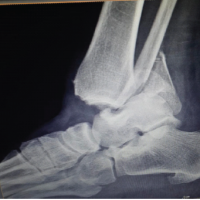

A 12-year-old, right-hand-dominant female was brought to us by her parents with complaints of pain in the left wrist for the past 4 months, swelling since 3 months, without any history of fever, effusion, weight loss, or any similar complaints in family members. On examination, there was a swelling of (5 × 4 cm) in size, non-fluctuant, non-pulsatile, non-compressible, without any local rise of temperature. Hand function and grip strength were decreased on the left side as compared with the right side and there was no neurovascular deficit. Radiographs obtained showed a metaphyseal, osteolytic lesion with cortical breach and no periosteal reaction, which seemed to point toward an osteoclastoma of the distal radius; the epiphysis seemed to have been fortunately spared (Fig. 1 and 2). This was followed up with a biopsy, which confirmed our clinical and radiological findings. The child was diagnosed with a Campanacci Grade 3 GCT of the left distal radius and planned for wide local excision and ulnar translocation.